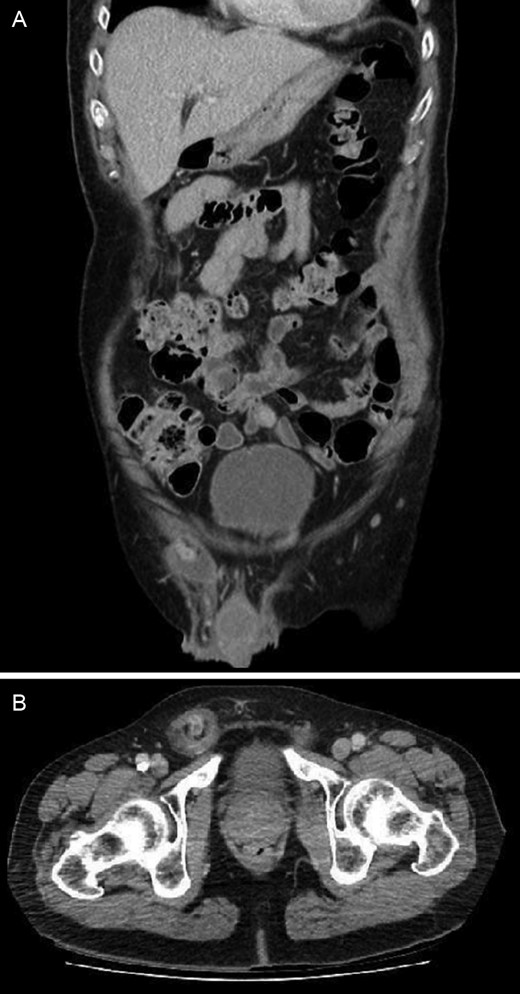

A 72-year-old man presented to a regional Australian hospital with a painful, irreducible right inguinal hernia. He did not have any obstructive symptoms. On examination, he had a 3 cm, tender inguinal lump with overlying skin erythema which was not reducible. He proceeded to CT scan which identified an Amyand’s hernia with radiographic features of appendicitis within the hernial sac with luminal dilation and enhancement of the appendiceal wall (Fig. 1). There was no bowel dilation to suggest obstruction.

CT showing right inguinal hernia containing contrast filled appendix with dilated lumen, wall enhancement and free fluid within the hernial sac: (A) coronal view and (B) axial view.